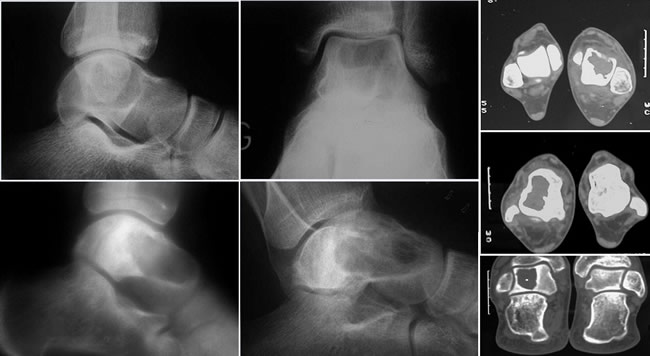

Traitement d'une Tumeur à Cellules Géantes du radius

Traitement d'une Tumeur à Cellules Géantes du tibia

Traitement d'une Tumeur à Cellules Géantes du fémur

Aspect tomodensitométrique typique

Persistance d'une corticale continue, parfois en pointillée

Respect du cartilage articulaire

Pas d'envahissement des parties molles

Technique opératoire

Comporte 4 temps :

1°) véritable éventration de la cavité tumorale suivie.

2°) d'un curettage long et patient.

3°) puis d'une ostéosynthèse.

4°) avant le comblement de la cavité tumorale avec du ciment acrylique.

(2 malades ont subi une cryothérapie associée).